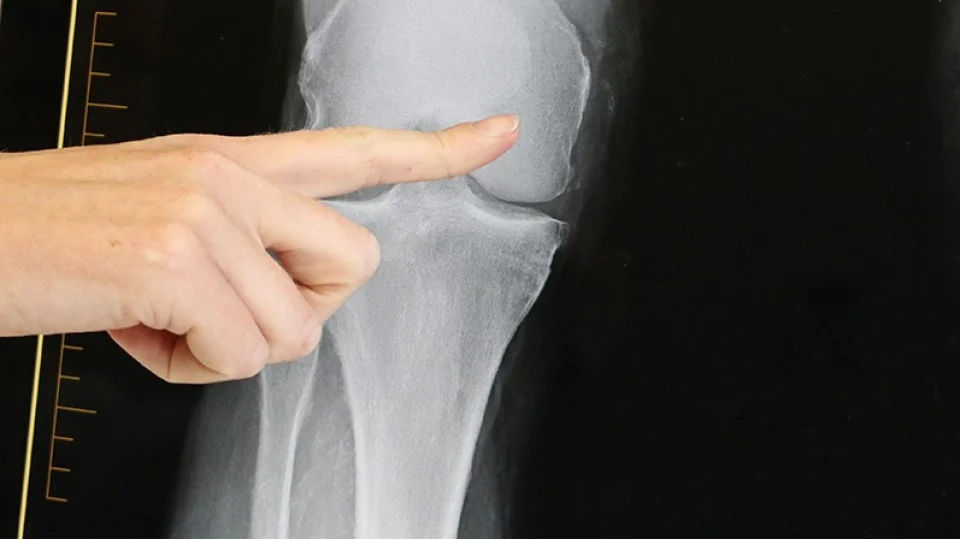

Menisküs, diz ekleminde "C" şeklinde yer alan kıkırdak yapıdır ve vücut ağırlığını dengeli dağıtarak ekleme binen baskıyı azaltır. Ancak ani hareketler, spor sırasında yapılan bilinçsiz uygulamalar ve yaşa bağlı yıpranmalar bu yapının yırtılmasına neden olabilir.

Yırtığın Özellikleri

Menisküsün dış kısmındaki küçük yırtıklar bazen kendiliğinden iyileşebilirken, iç kısımdaki yırtıkların veya büyük ve karmaşık yırtıkların iyileşme olasılığı düşüktür. Bu nedenle tedavi planı yırtığın büyüklüğü, yeri ve tipi dikkate alınarak yapılır.